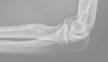

2.6.4 Radionuklidové metody (Daniela Chroustová) 35